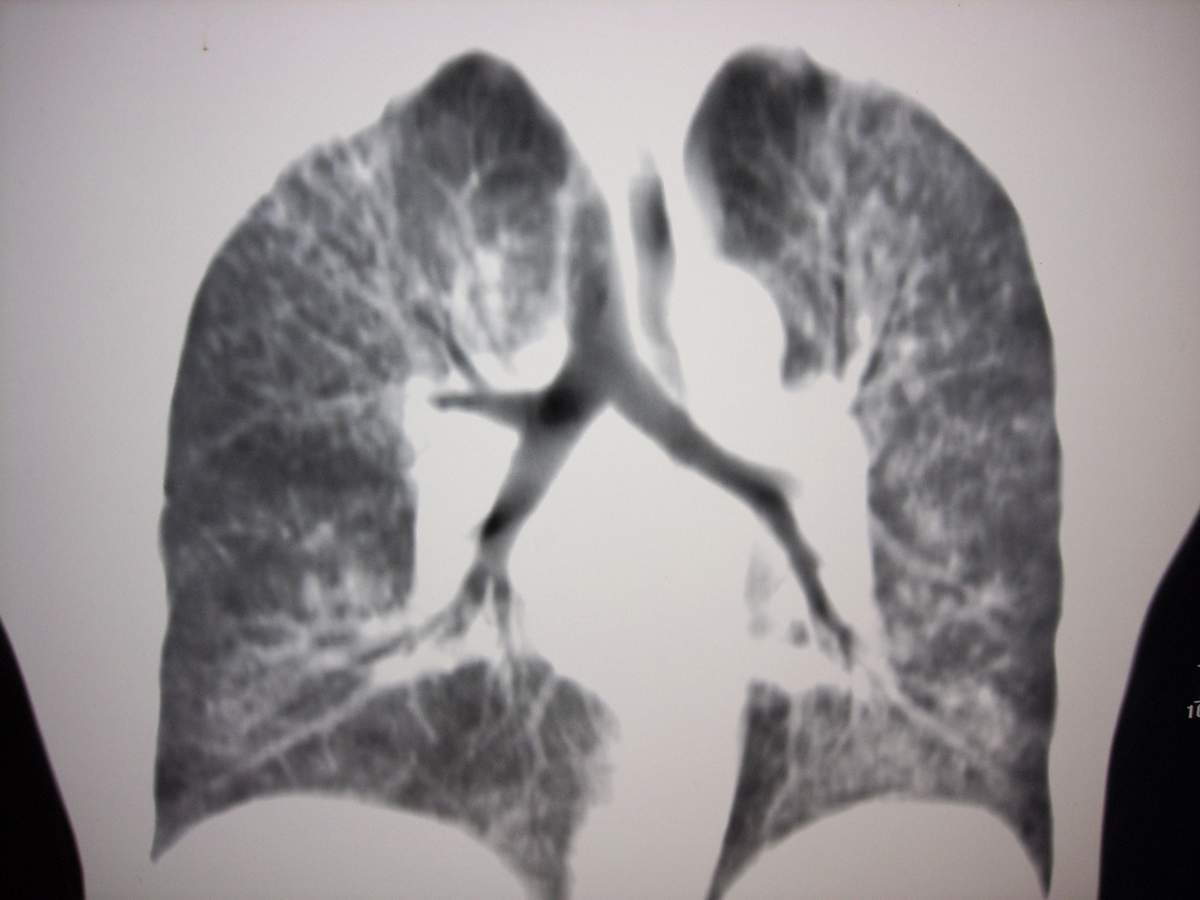

女,咳嗽、气喘2月余。

双肺弥漫性病变, 冠状重建肺血管增粗,建议继续上传详细临床资料,x线片

双肺弥漫磨玻璃样影,边界不清,似蝶翼征。肺纹理增多。

考虑:肺泡蛋白沉积症。建议临床进一步检查。